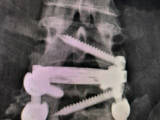

Una vez que hemos llegado al disco intervertebral separamos el músculo psoas hacia un lado y el peritoneo con las arterias hacia el otro. Con material especialmente diseñado para el OLIF realizamos la discectomía, posteriormente prepararemos el espacio intervertebral para introducir una caja intersomática y realizar una fusión vertebral.

Mal posición de la caja. En el OLIF accedemos de una manera oblicua a la vértebra, pero la caja intersomática debemos poner en el eje lateral por lo que debemos hacer una maniobra para dejarla correctamente alojada, puede ocurrir que la caja este excesivamente oblicua y que en la zona contraria al acceso la caja intersomática entre en el canal lumbar pudiendo lesionar la duramadre o alguna raíz nerviosa.

Fractura vertebral. Al preparar el espacio intervertebral podemos fracturar el cuerpo vertebral, o situar la caja inersomatica atravesando el cuerpo vertebral. Si esto ocurre lo que debemos hacer es dar la vuelta al paciente y realizar una instrumentación posterior.